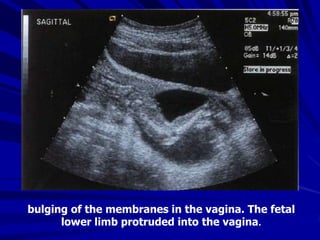

bulging of the membranes in the vagina. The fetal

lower limb protruded into the vagina.

bulging of themembranes in the vagina. The fetal lower limb protruded into the vagina.